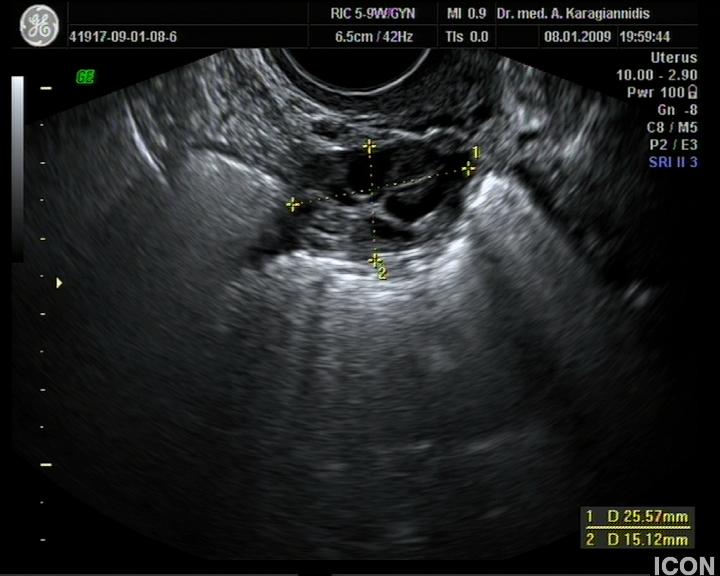

Κολποσκόπηση

Η κολποσκόπηση είναι μια εξεδικευμένη εξέταση που αφορά τον τραχήλου της μήτρας και πραγματοποιείται με τη βοήθεια ενός ειδικού οργάνου του κολποσκοπίου.